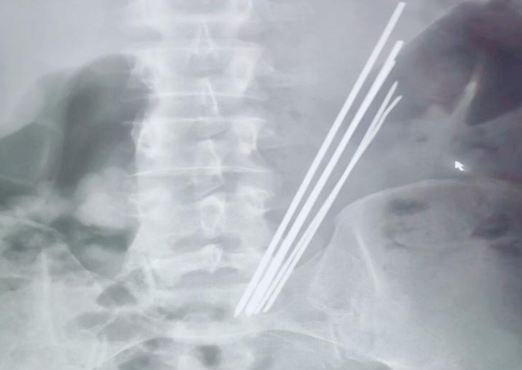

李恒副主任醫師詳細了解上述情況后,立即與內鏡中心麻醉師張玉河醫生溝通,暫時無法確認異物是否嵌頓入胃壁,以及其嵌入深度,普通胃鏡的刺激極有可能加劇患者痛苦,為異物取出造成阻礙,無痛胃鏡相對而言,患者痛苦較小,避免了配合度不高等情況,但與此同時,因異物存留于胃腔內時間較長,考慮金屬質地,且數量較多,操作過程中必然會面臨很多棘手問題,并發呼吸困難、大出血的風險。消化內科一病區李主任和麻醉醫師張玉河認真翻閱患者相關信息,制定出嚴謹、詳盡的治療方案。征得患者及家屬同意后,又一場攻堅戰展開了......進鏡至胃腔,可見5個長條形金屬異物滯留,表面光滑,粘液附著,抓取難度非常之大,需在胃腔內不斷調整方向,確保異物以豎直狀態隨胃鏡緩慢退出,避免異物通過食管及口腔時造成的二次損傷,經過反復不懈努力,最終異物全部安全取出,長條狀金屬異物最長達16cm左右?;颊呒覍匐y掩興奮之情,不停的念叨著“謝謝,謝謝”,內鏡下的異物取出讓他們的親人免受手術之苦,同時也減輕了經濟負擔。